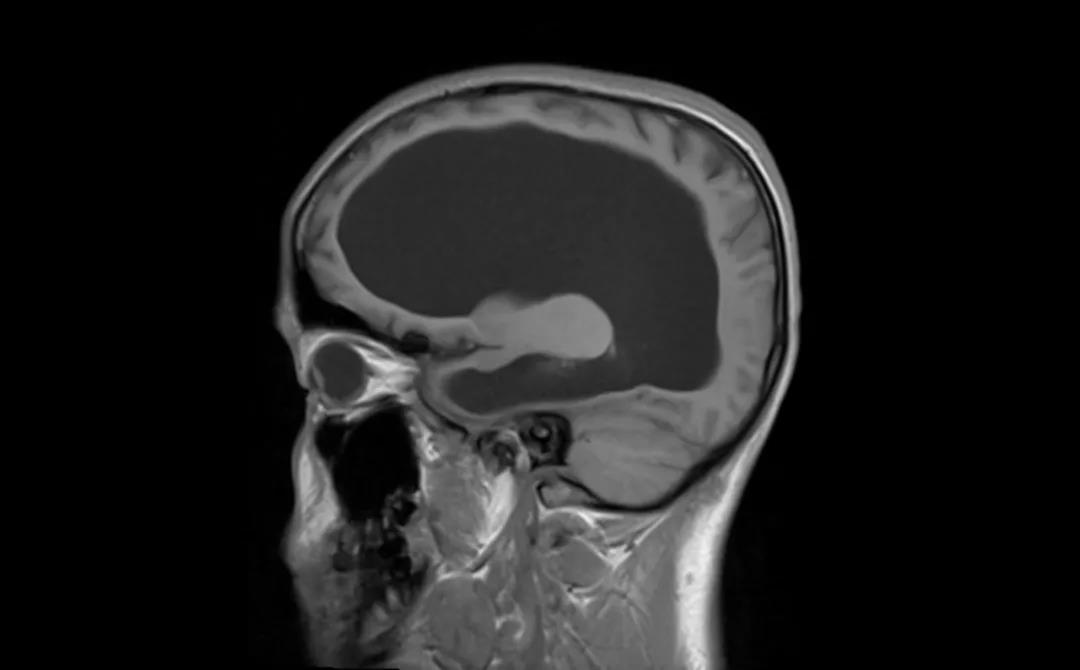

患者術前 CT

腦積水積的不是水,而是腦脊液過多,是由于顱腦疾患使得腦脊液分泌過多或(和)循環(huán)、吸收障礙而致顱內腦脊液量增加,腦室系統(tǒng)擴大或(和)蛛網膜下腔擴大的一種病癥。